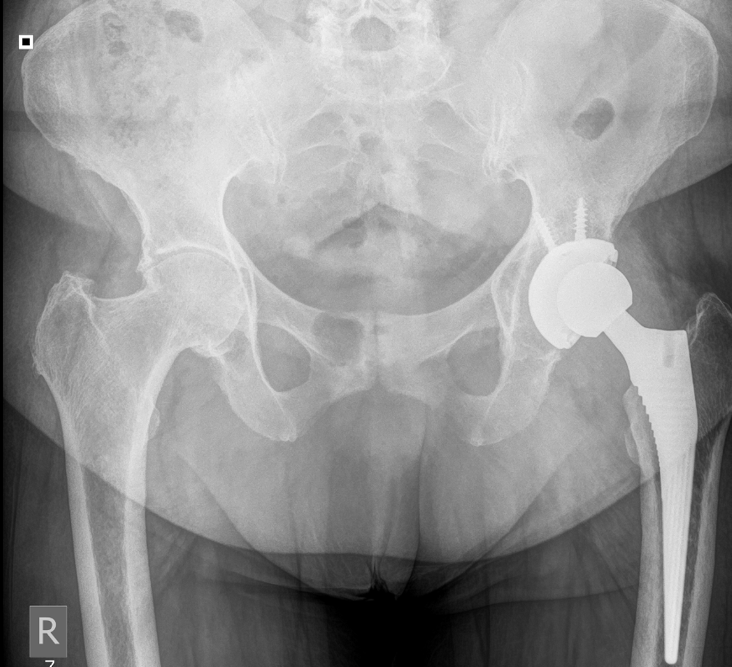

Although no instability or gross motion of any of the components was detected intraoperatively, the acetabular cup was fixated with two screws to reinforce the stability of the construct. The post-operative protocol comprised non-weight-bearing for the first 2 weeks, partial weight-bearing for the following weeks and initiation of full weight-bearing at 6 weeks postoperatively. At the 2-month follow-up visit the patient was able to weight bear and walk but complained of pain when rising from the seated position and during the first steps. The symptoms were improving during walking. Clinical examination revealed a leg-length discrepancy of approximately 2 cm, but the radiological evaluation showed no pathological findings. The patient was encouraged to continue rehabilitation, return to moderate daily activities, but to avoid overload. Six months postoperatively, the symptoms significantly worsened with severe pain during loading and a “snapping” feeling on every step. A thorough laboratory investigation was obtained showing no increase in inflammation markers and no other pathological findings. Further imaging with new X-rays, MRI, and CT was also inconclusive (Figs. 3, 4, 5).

Figure 3: No periprosthetic lucencies at the 6-month post-operative X-ray.

Figure 4: Pre-operative computed tomography scan with no sign of acetabular cup loosening.

The patient was scheduled for revision arthroplasty. The surgery was undertaken 2 weeks after, and loosening of acetabular cup was confirmed intraoperatively. There were no signs of loosening of the femoral component or infection. Samples were sent to detect possible infection. Loosen cup was removed and exchanged to a larger tantalum cup. The post-operative course was uneventful, and a full recovery was succeeded. At 2, 6, and 12-month follow-up the patient had a painless range of motion and had fully returned to her activities (Fig. 7). At a final follow-up at 18 months, the patient presented with a significant improvement in function and quality of life compared to the pre-operative evaluation. Her pain was limited from a Visual Analog Scale (VAS) = 7 preoperatively to VAS = 2 postoperatively.

Figure 7: Post-operative imaging after revision surgery.